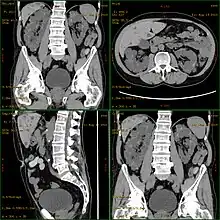

CT scan showing autosomal dominant polycystic kidney disease

Polycystic kidney disease can be ascertained via a CT scan of abdomen, as well as an MRI and ultrasound of the same area.[23] A physical exam/test can reveal enlarged liver, heart murmurs and elevated blood pressure.[1]